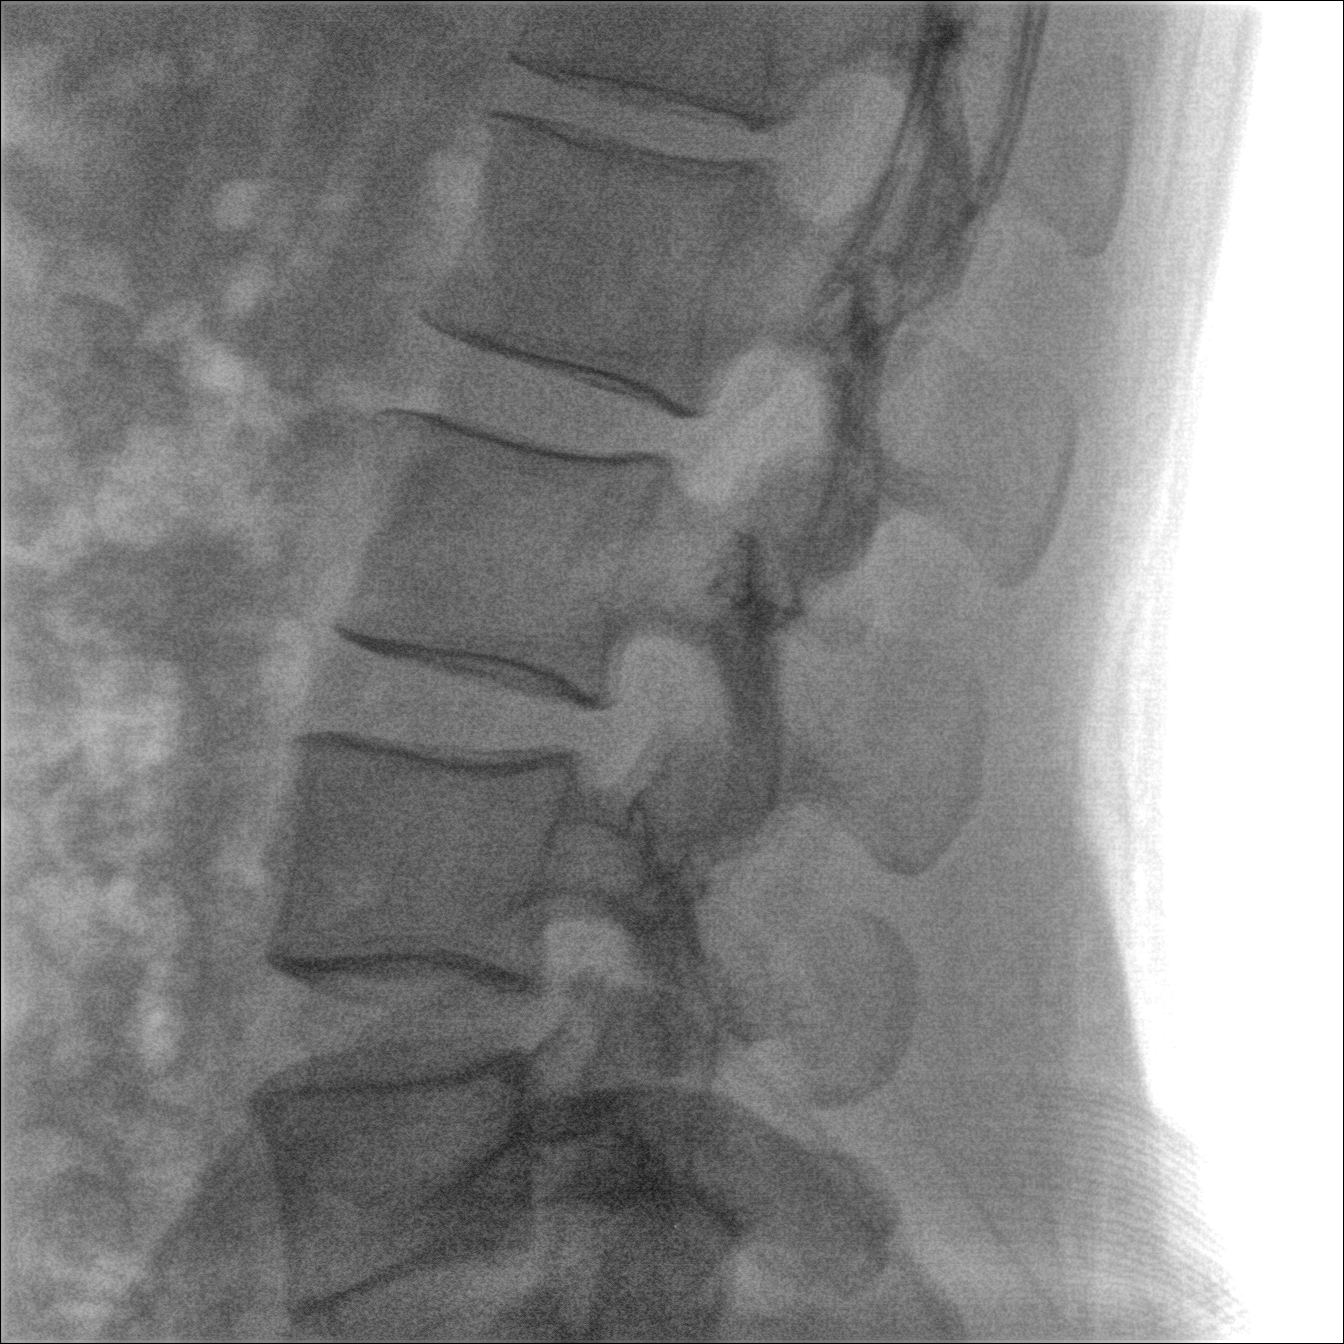

Clinical picture

臨床圖片